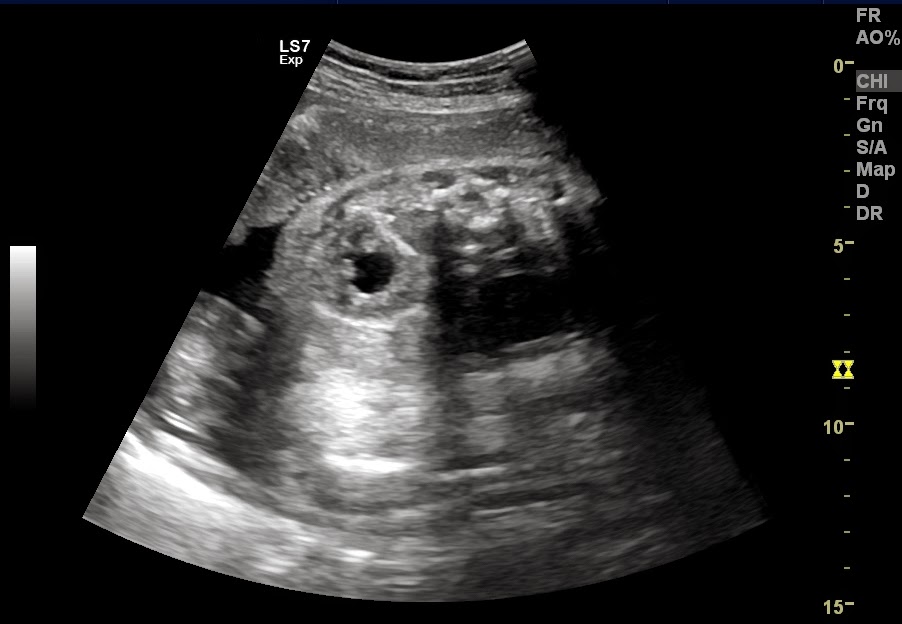

Ultrasound imaging Sonography of a case of bilateral fetal hydronephrosis Hydronephrosis Kidney Baby “hydronephrosis” is a descriptive term for the appearance of a kidney containing more than normal amounts of urine in the. hydronephrosis is a condition, affecting about 1 in 100 babies, where urine overfills or backs up into the kidney, causing the. dilation of the fetal renal collecting system, antenatal hydronephrosis (anh) or pyelectasis, is one of the. Hydronephrosis Kidney Baby.